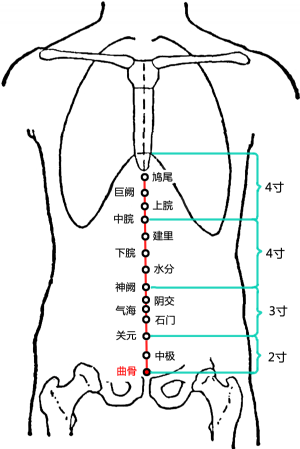

標準定位:曲骨穴在下腹部,當前正中線上,恥骨聯合上緣的中點處[6]。

曲骨穴位於腹正中線,臍下5寸,恥骨聯合上緣上方凹陷處[6]。

曲骨穴位於下腹部,當前正中線上,恥骨聯合上緣。仰臥取穴[6]。

曲骨穴在下腹部的位置

曲骨穴在下腹部的位置